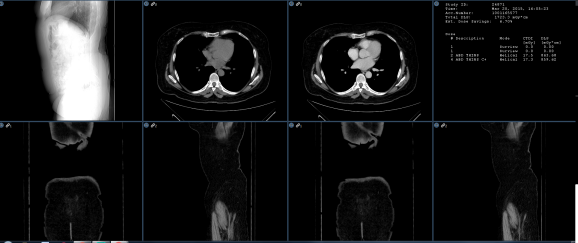

Selected Study

When this option is selected along with the Grids matrix layout, a selected study in the thumbnail panel can be designated for image frame loading. When the user clicks on the thumbnail study header a yellow border will surround the images. Those will load into the frames in the same order of the thumbnail study as shown below.

When loading priors, selecting the study header and highlighting the series will only load those selected priors after grid matrix frame layout is created.